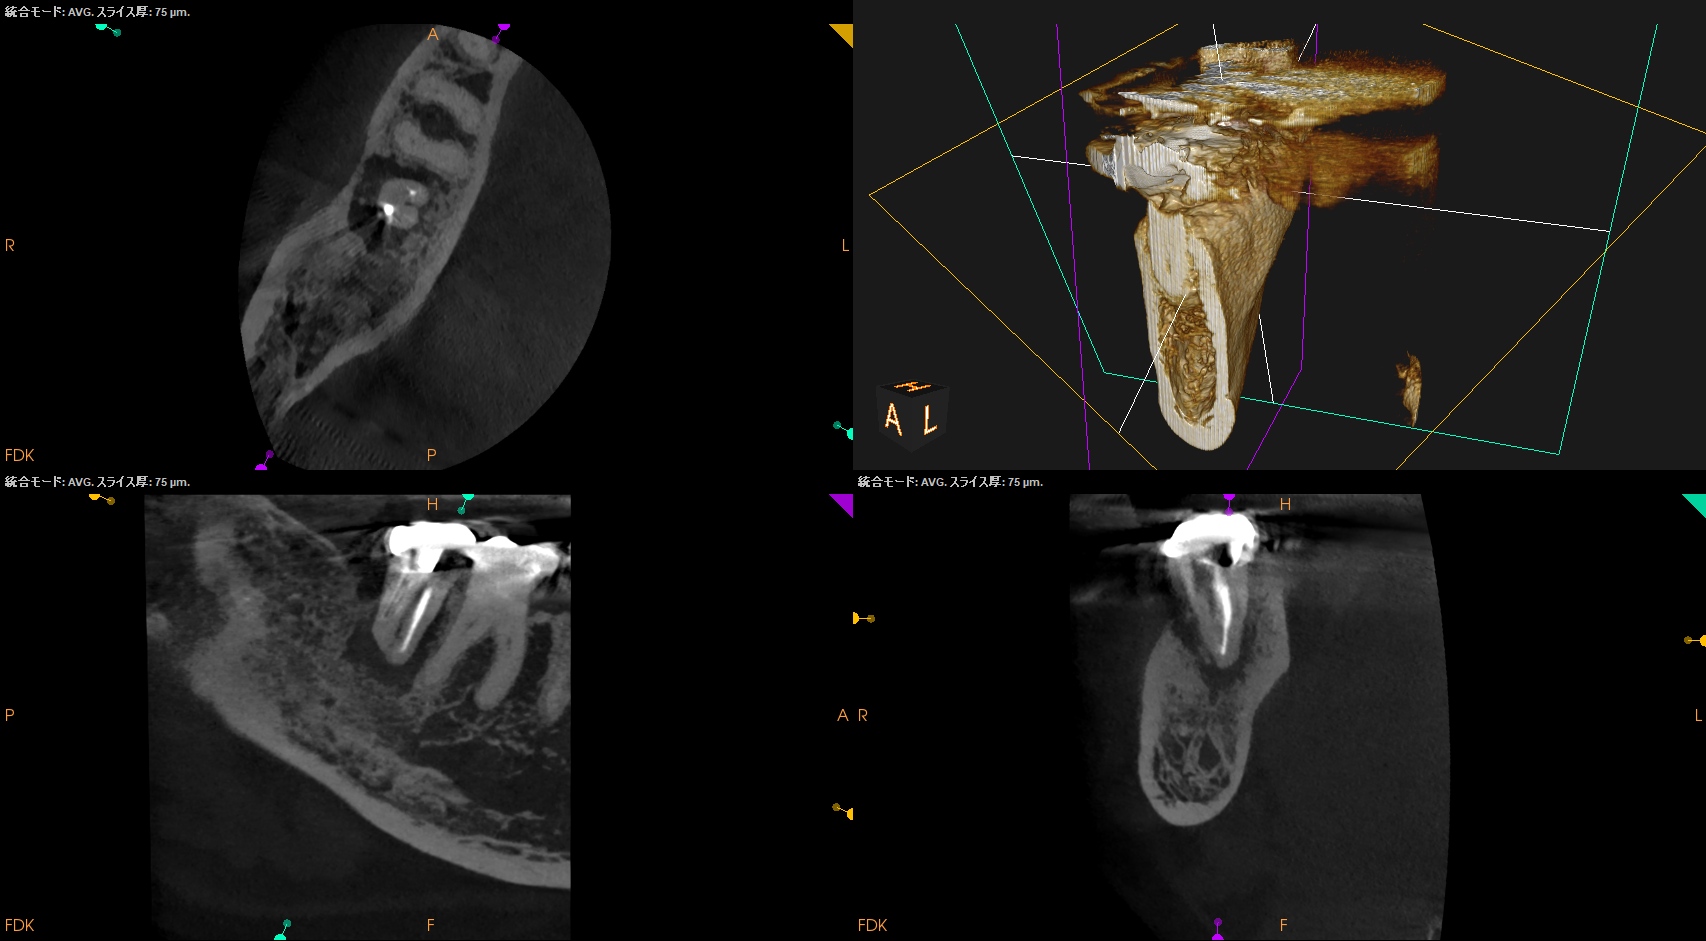

PA, CBCTを撮影した。

ML

MB

D

問題はないだろう。

この歯牙の根尖部の歯槽骨が回復するかどうか?は時間が解決する。